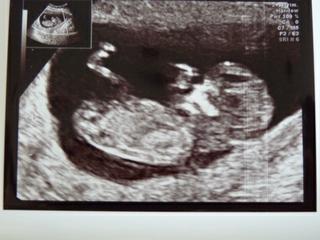

Ahojte zienky, cely den sme boli v nemocnici, som unavena ako pes. Ale stalo to za to 🙂 Ked mi sestricka prilozila ultrazvuk na brusko a ja som zbadala,ze mam v brusku meleho cloviecika, tak mi z oka vypadla taka velka slza, ze som si to uvedomila az po chvilke. Malinke je v poriadku, chvilku nam nechcelo ukazat druhu nozicku, ale nakoniec ukazalo a ma 2 nozicky a 2 rucicky a ked sa zacal ultrazvuk, tak nam aj zakyvalo, lebo vystrelo rucicku, no sestricka skonstatovala,ze je to velmi zive dietatko a ze je vsetko ako ma byt,ze ma dost miesta a je v poriadku. Upravila nam termin porodu, kedze babatko je vacsie, tak nie sme v 11+4 ale sme v 12+1. Takze datum porodu nie je 6.10. ale 3.10.10. Velmi sa tesime,ze sme ok. Este mi zobrali krv a vdaka bohu som neodpadla, co som velmi rada, lebo obycajne vzdy odpavadavam pri kazdom odbere a pri kazdej injekcii. Ale drzali sme sa statocne. Dalsiu poradnu mame o 6 tyzdnov a to uz hadam budeme aj vediet co to bude. Inak hned sme volali do Dublinu a objednali sme sa na NT screening a ideme nan v stredu o 10:40 mame objednavku. Tak aspon budeme mat za tyzden vsetko za sebou a budeme ovela kludnejsi, Dufam,ze vsetko bude ok a vsetko dobre dopadne. Uz som si dnes aj kupila zopar triciek s dlhym rukavom a jedno take elegantnejsie, tak sa tesime No tolko odomna. Idem sa vystriet mam dost. Dufam,ze zajtra cestu do Dublinu zvladnem predsa len 4 hodiny v buse ☹ Prepacte,ze neodpisem na to co ste tu pisali ale slubujem,ze ked sa vratime z Dublinu tak potom si najdem cas a urobim tak. Opatrujte sa a nech ste vsetky ok a hlavne zdravucke pa pa

krásná fotečka! 😵

emily, krásná fotečka. A držím palečky, aby bylo na NT vše ok 😵

emily kraaaasna fotecka .... drzim na NT vsechny palce, ozvi se az budete mit vysledky ....

Emily, tak naaaadhera. Aj fotocka, aj sprava, este nech ti tie testy vyjdu dobre a uz sa len tesit mozes a kaslat na sefku. Tesim sa z teba.